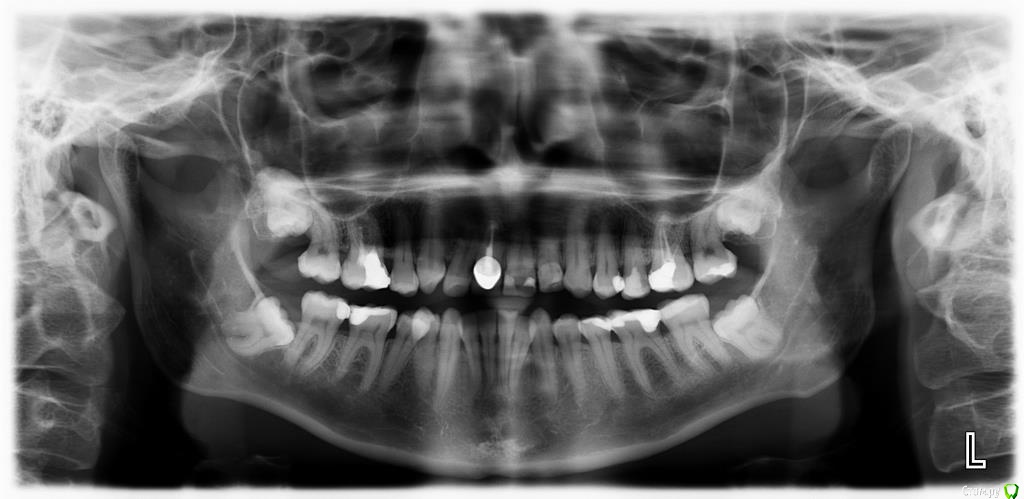

Galaola Опубликовано 28 февраля, 2016 Поделиться Опубликовано 28 февраля, 2016 Добрый день! Мне 36лет. Удалена правая верхняя 4 в детстве. При выборе ортодонта остановилась на варианте без удаления зубов, но с сепарацией зубов НЧ. Через 6 мес лечения ортодонт заявляет об удалении правой нижней 8 как минимум, а лучше всех. Прошу совета и мнения специалистов. Насколько необходимо удаление 8-к? Возможно ли расширить ВЧ и каким образом? Возможно ли подготовить место под имплант отсутствующей 4 или поставить адгезионный мост? Спасибо. Ссылка на комментарий

Brigita Опубликовано 9 марта, 2016 Поделиться Опубликовано 9 марта, 2016 8ки уже не прорежутся, их нужно удалять. Даже прорезанные зубы мудростм все 4 несут жевательную нагрузку около 3%, то есть они абсолютно в Вашем случае ненужные.Имплантация каких зубов планируется? Ссылка на комментарий